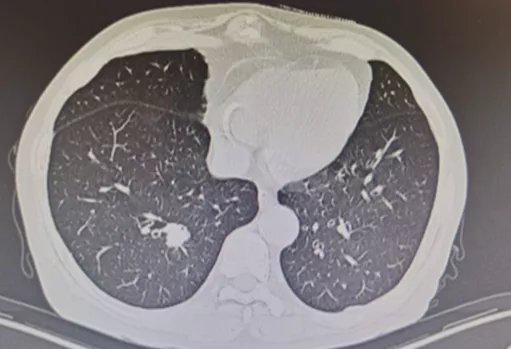

七、多发性GGO问题

多发性GGO可以是一个结节为主、有多个结节,我们叫主病灶和次病灶。它可能同时发生,也可能在随访过程中逐步发生。各种情况都有,它的意义是不一样的。关于多发性GGN的诊断,病因更多,病情更复杂,所以我们处理起来更困难一些。

基于mGGNs中主病灶的临床决策

我现在特别赞成文献上提出的按主病灶为准来处理,也叫突出病灶,这种病人手术效果也很好。所谓的「打地鼠原则」,地鼠往上一冒头,就用锤子把地鼠打下去。对于多病灶来说也是一样,哪个病灶出了问题就处理哪个病灶,就是「打地鼠原则」。这是我认为目前临床上比较好的多发性GGN处理的一种方式,大家可以借鉴。